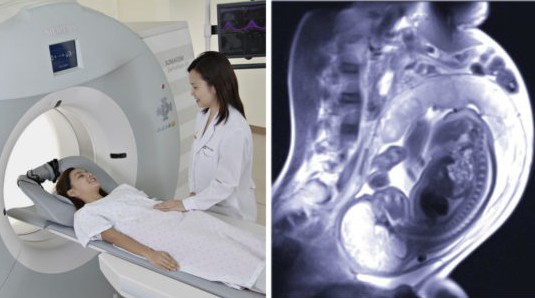

МРТ плода: когда и как

Магнитно-резонансная томография может назначаться будущей матери приблизительно с 18-недели беременности (раньше – только по экстренным показаниям), целесообразность обследования определяется врачом. Перед МРТ плода необходимо снять любые металлические предметы (пирсинг, украшения, часы). Беременная женщина ложится на исследовательский стол, принимает комфортную позу. Возможность прерывания процедуры при дискомфорте пациентки обеспечивается специальным звонком.

Длительность обследования составляет примерно 30-45 минут. Допускается присутствие сопровождающих лиц, если это необходимо для спокойствия будущей матери. Проблема громкого стука, который издает аппарат МРТ, решается с помощью слуховой защиты. Не нужно переживать за ребенка, любые звуки воспринимаются зародышем через околоплодные воды, ослабляющие шум. Как правило, результаты можно узнать на следующий день.